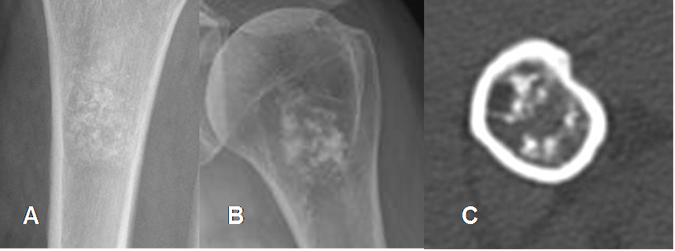

Fig 36. Matriz condroide.

A: Rx AP. Calcificaciones puntiformes y en coma, de un encondroma.

B: Rx AP y C: TAC axial. Calcificaciones en palomitas de maíz, por encondroma.